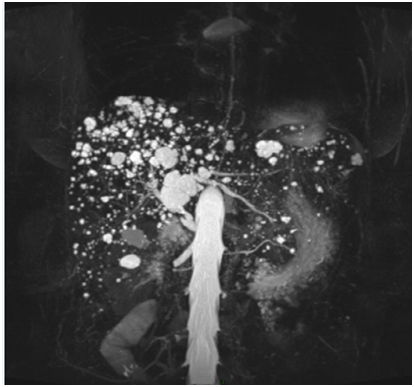

A 63years old female noted to have non-specific hepatic abnormality in a follow up chest CT for infection. The subsequent MRCP demonstrated numerous cystic lesions throughout the liver which showed no communication with the biliary tree (Figure 1). Diagnosis of Von Meyenburg Complex has been made. No further management or investigation is required.

Figure 1 Diagnosis of von meyenburg complex.

The biliary hamartomas are consistent of small clusters of dilated cystic bile ducts which are not communicating with the biliary tree. On imaging, they appear as multiple small round or irregular lesions throughout the liver with peripheral predominance. No enhancement in the post contrast images.3 The radiological differential diagnoses include multiple liver cysts and hepatic metastases.